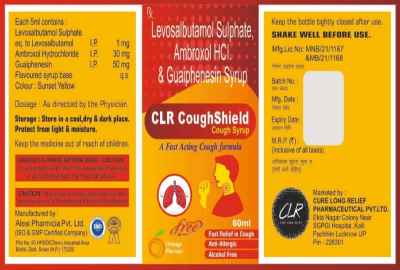

CLR-pharmaceutical is an certified company. it is considered to be one of the fastest growing Pharmaceuticals company. We have a dedicated team of technical professionals with extensive experience in Pharmaceuticals industry who are committed to produce various formulations with stringent quality standards, keeping in mind the social responsibility to contribute better health care of the society. All our manufacture are WHO certified companies in Pharma & FSSAI & ISO registered companies in Nutritional products. Our products are high quality products with beautiful packing manufactured under strict quality control as per schedule M –GMP guideline. The formulation objective of our company is to provide scientifically sound quality product and solution to cure disease and improve the quality of life.

Chew this medication thoroughly and swallow, usually once daily or as directed. Follow all directions on the product package, or take as directed by your doctor. Do not take more than the recommended dosage. If you have any questions, ask your doctor or pharmacist.

Take this medication regularly in order to get the most benefit from it. To help you remember, take it at the same time each day.